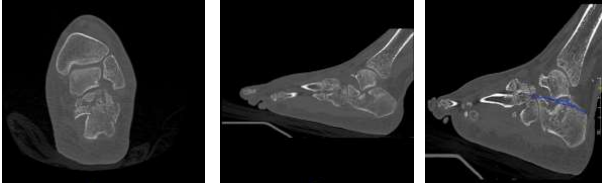

A computed tomography (CT) scan was performed to delineate the precise fracture anatomy, classify the fracture pattern according to the Sanders system, and inform treatment strategy.

The CT images revealed a Sanders type IV fracture, characterized by three fracture lines and four main posterior facet fragments (Figures 3 and 4). This complex fracture pattern demonstrates disruption of both the intra-articular and extra-articular components of the calcaneus. Furthermore, the crucial angle of Gissane measured approximately 165 degrees (Figure 5). This value significantly exceeds the normal range of 115-145 degrees, indicating significant posterior facet height loss and a potential for compromised joint congruity and long-term functional outcomes.

Figure 3

Figure 4

Figure 5